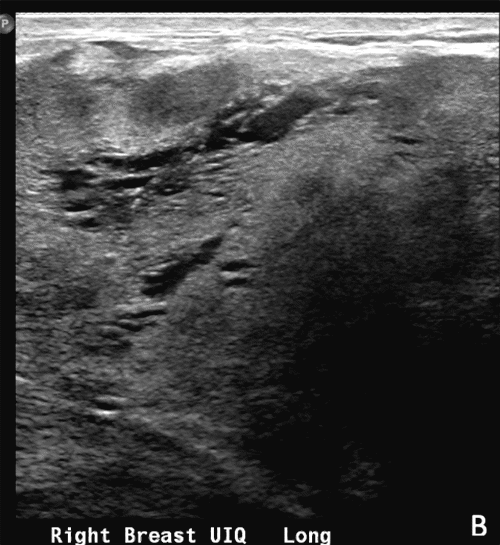

Figure 2. Views of Breast. Published with Permission

B) Right Upper Inferior Quadrant View of Breast on Long Axis

The patient was scheduled for surgery and underwent a palpation-guided excisional breast biopsy. A lateral hockey stick incision was made along the inframammary fold, and an anterior skin flap was developed. Using palpation as guidance, we continued with dissection, and thick adhesions were taken down. The capsule of the mass was bluntly and sharply dissected until the mass was only attached to the subcutaneous tissue of the medial superior breast (Figure 2).